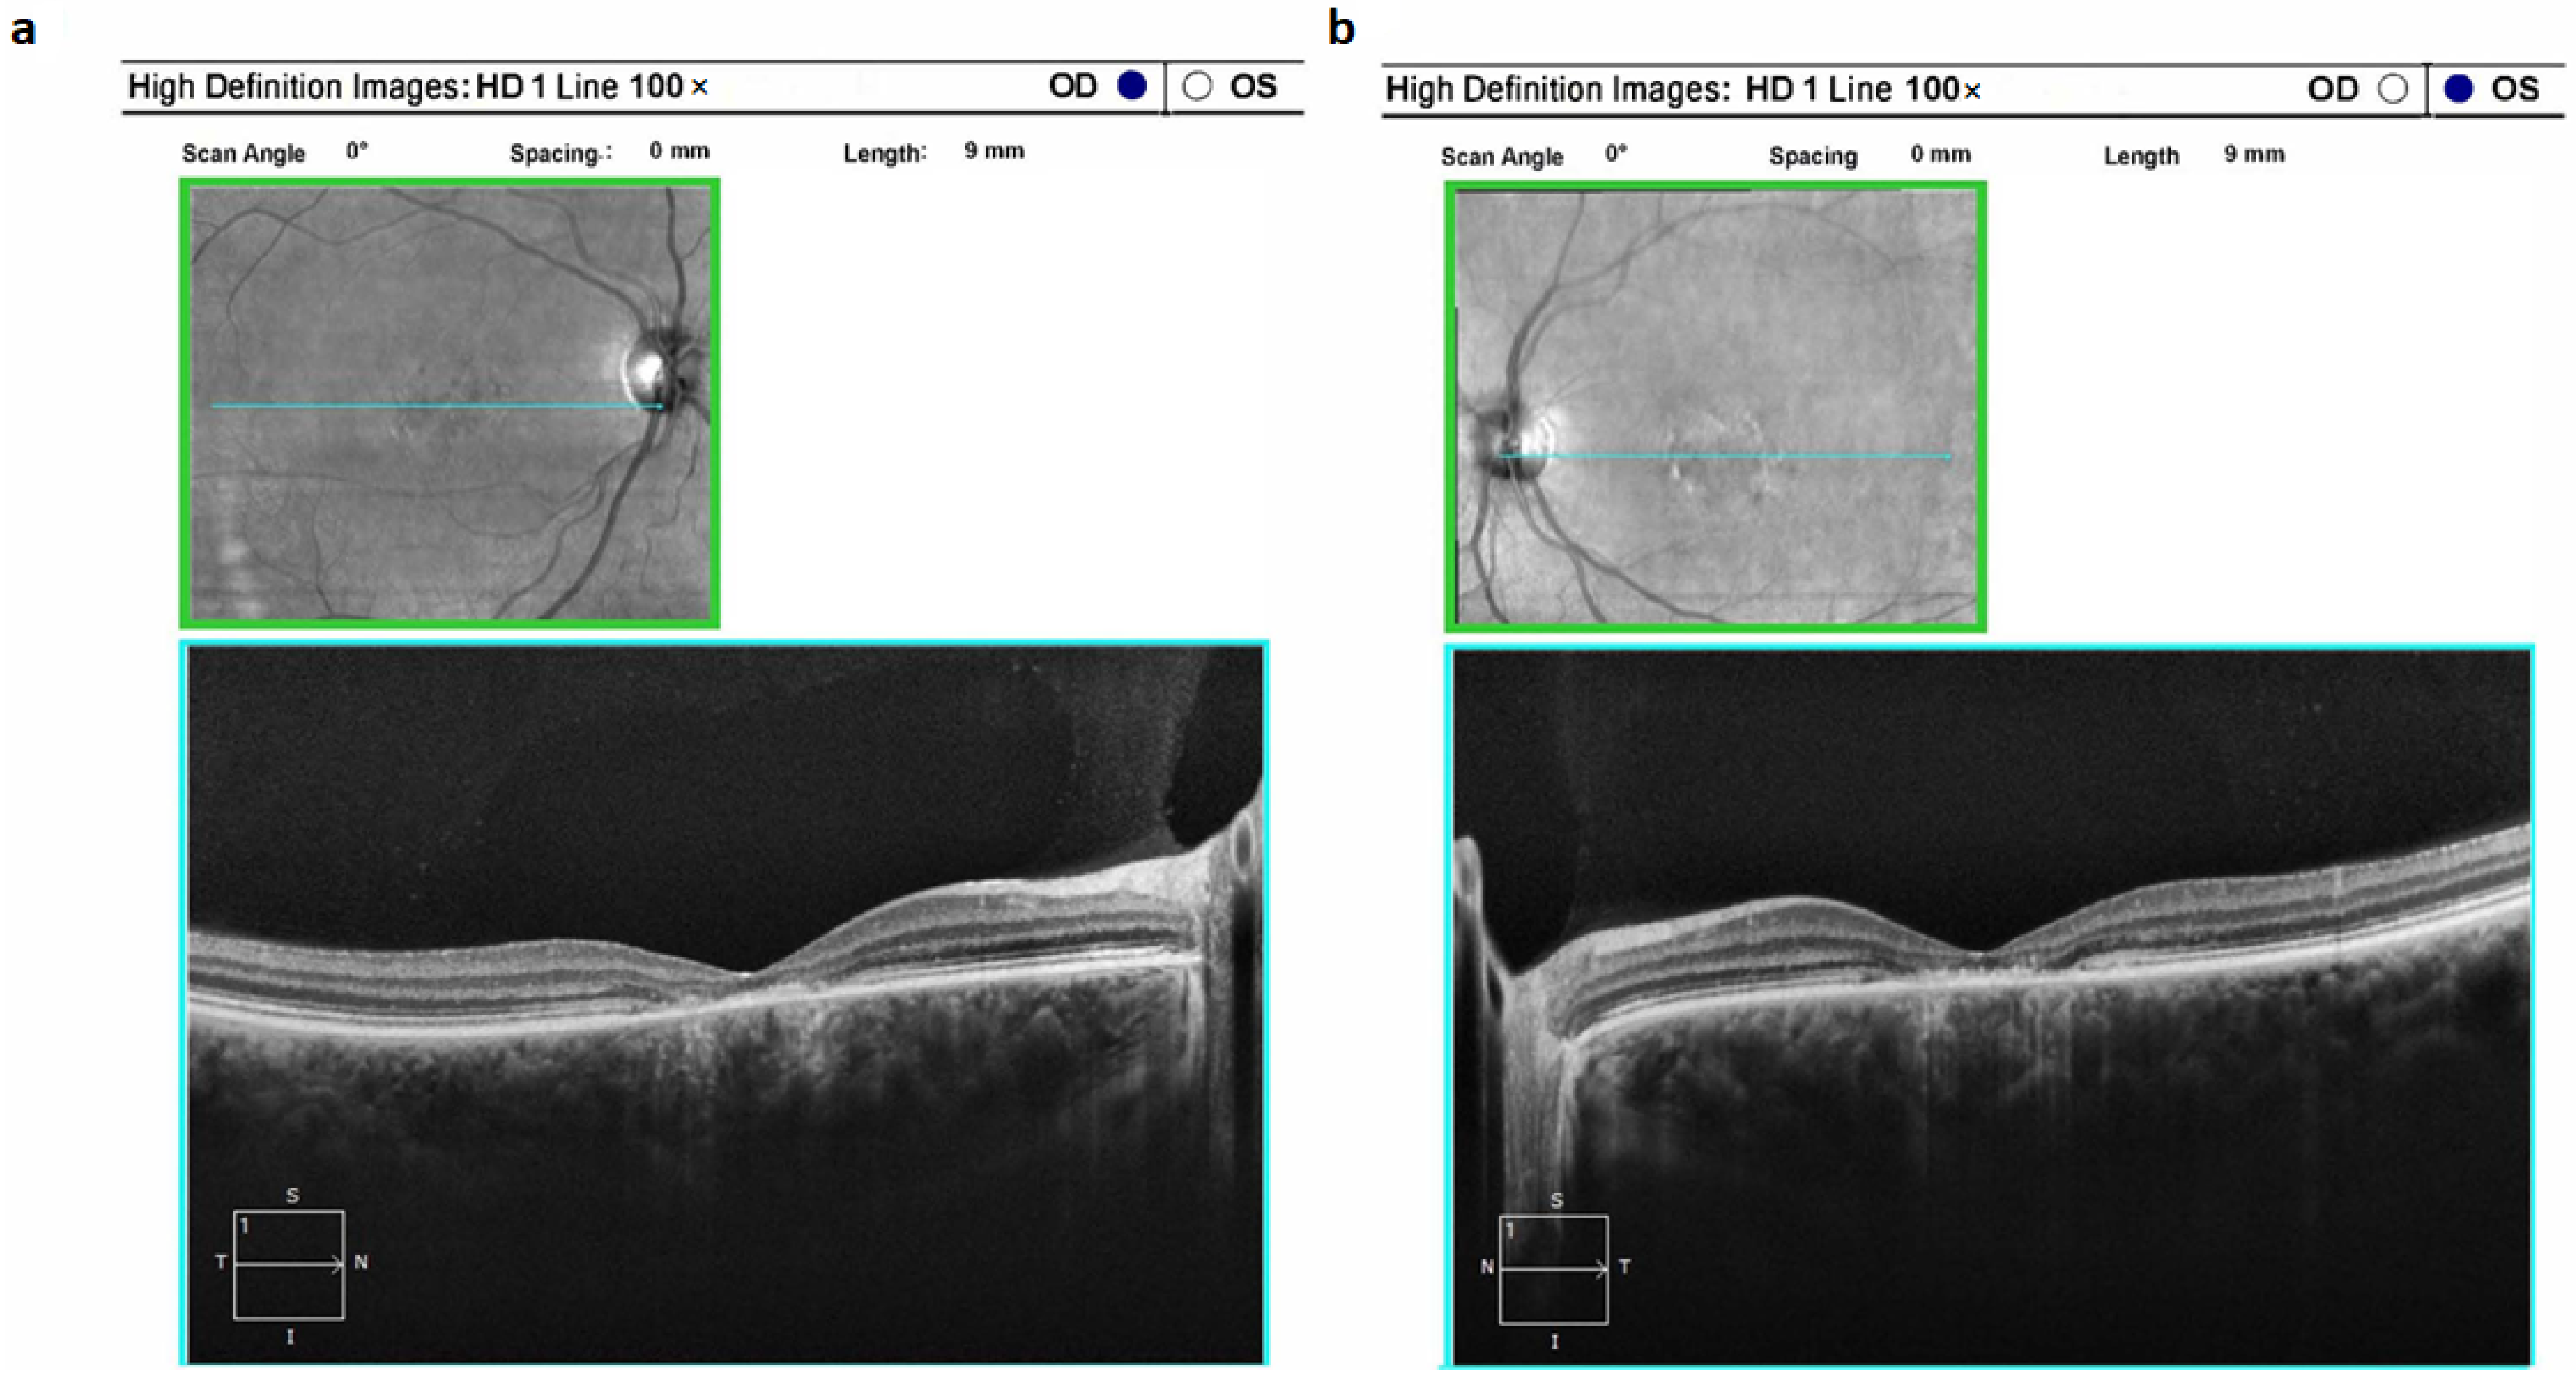

Typically, STGD1 manifests as a classical clinical profile. Ophthalmoscopic examination commonly unveils a distinctive macular region characterized by atrophic changes displaying a metallic sheen; notable is the absence of observed pigment deposits. Notably, the atrophic alterations are limited to the paramacular region, without extending further. These structural observations are in alignment with the findings from electroretinography (Figure 2).

Figure 2. Optical coherence tomograms of the right (a) and left (b) eyes in a patient (ID-16) with Stargardt’s disease 1 (STGD1).